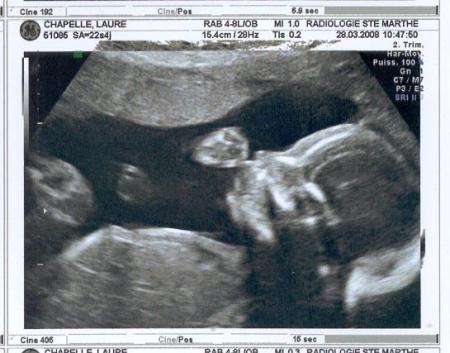

échogaphie du 2ème trimestre.

27/11/2008 20:06 par lauremanulucas

nous sommes le 28 mars 2008 et maman est enceinte d'un peu plus de 4 mois. pour sa plus grande joie, elle a apprit que j'etais un garçon! attention les filles me vlà!